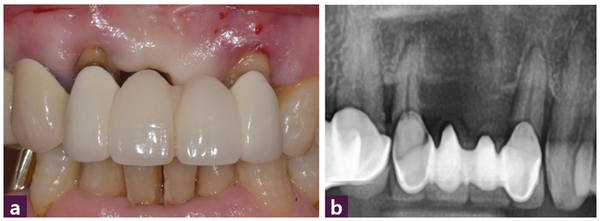

59세 남성 환자로 12번-22번 부위 4-unit bridge의 동요도로 내원했다. 식립 전 구강 내 사진에서 12번과 22번 치아의 치은 퇴측(gingival recession)이 관찰됐다 [그림 2].

Case 1은 [그림 2a]에서 보는 바와 같이 중등도 이상의 치주질환으로 인해 gingival recession이 동반된 상태인 가장 어려운 임상 case 중 하나이다. 왜냐하면 치은의 양과 높이, 그리고 골 양과 골 높이 모두 부족한 상태이므로 임플란트 식립에 성공하더라도 연조직 상태를 개선하지 못한다면 치료에 실패할 수 있기 때문이다. 치료계획으로 4개월 이후의 지연 식립은 골소실이 현재의 상태보다 많아질 것으로 판단해 배제했고 발치 후 즉시 식립 또는 4~6주 후의 연조직 상태에 따라 식립하는 방법을 고려했으나 환자의 심미적 요구가 크지 않아서 발치 후 즉시 식립을 선택했다.